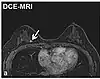

| Dynamic contrast enhanced | DCE | Measures changes over time in the shortening of the spin–lattice relaxation (T1) induced by a gadolinium contrast bolus.[76] | Faster Gd contrast uptake along with other features is suggestive of malignancy (pictured).[77] | ![]() | |